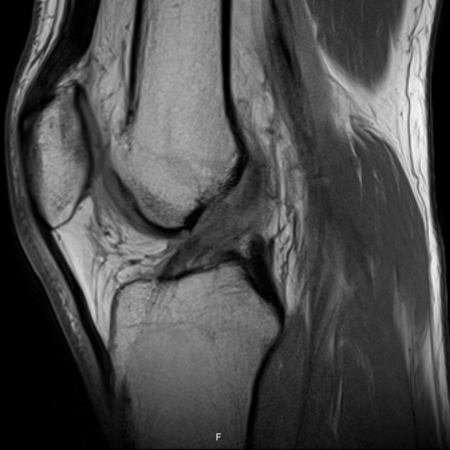

Det är bra att ha en rutin för hur man läser röntgenbilder generellt, även för MR-bilder. Ett exempel för knä kan vara så här:

Identifiera vilket som är lateralt (där man ser fibula). Börja laterala och gå mot medialt

Bläddra från ventralt till dorsalt, tillbaka till ventralt, upprepa vid behov.

Superiort till inferiort